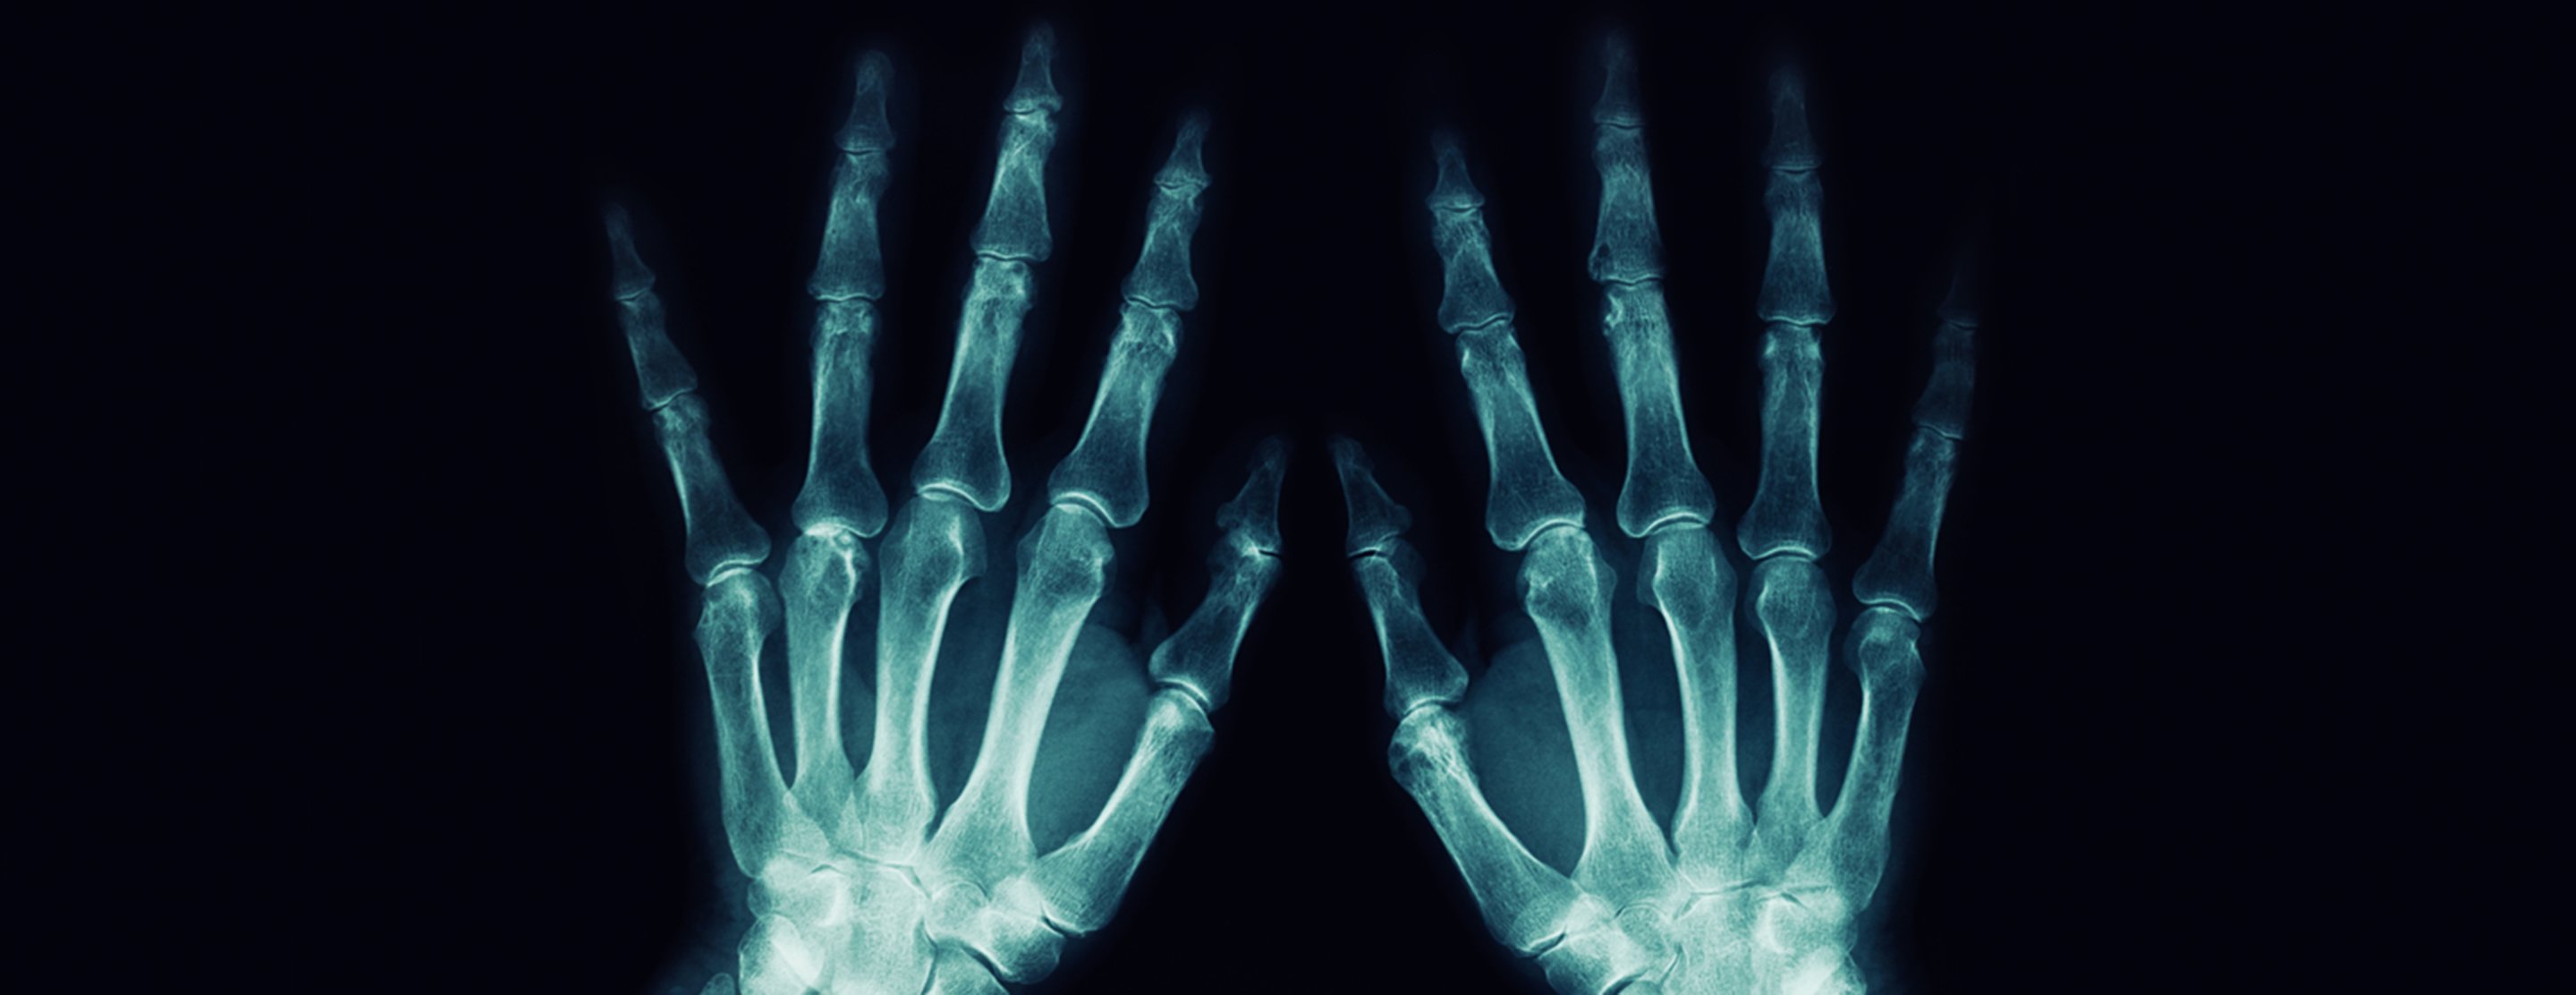

Hand x-ray

A hand x-ray is taken in a hospital radiology department or your health care provider's office by an x-ray technician. You will be asked to place your hand on the x-ray table, and keep it very still as the picture is being taken. You may need to change the position of your hand, so more images can be taken.